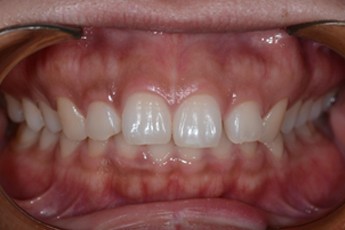

Before

After